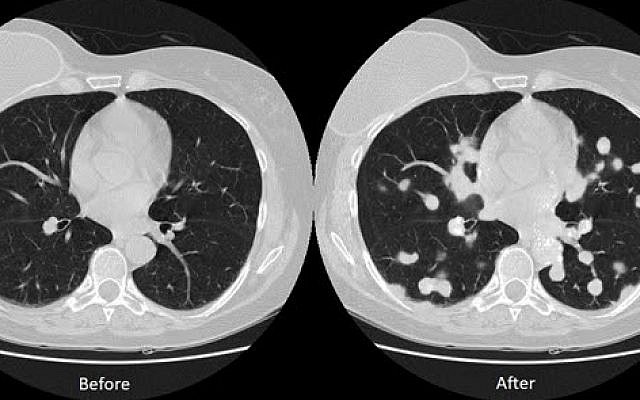

Исследователи BGU проверили эффективность атаки, обучив CT-GAN вводить или удалять рак легких с помощью бесплатных медицинских изображений из Интернета. Затем они наняли трех радиологов для диагностики набора изображений из 70 фальсифицированных и 30 аутентичных КТ-сканов.

Радиологи ошибочно поставили диагноз для 99% измененных снимков, которые показали злокачественные опухоли, и для 94% измененных снимков, на которых были удалены раковые поражения. И даже после того, как они узнали о таких манипуляции, эксперты все еще не смогли отличить подделанные изображения от подлинных, поставив неверный диагноз для 60% измененных изображений, которые ложно показали опухоли, и 87% тех, в которых были удалены признаки опухоли.